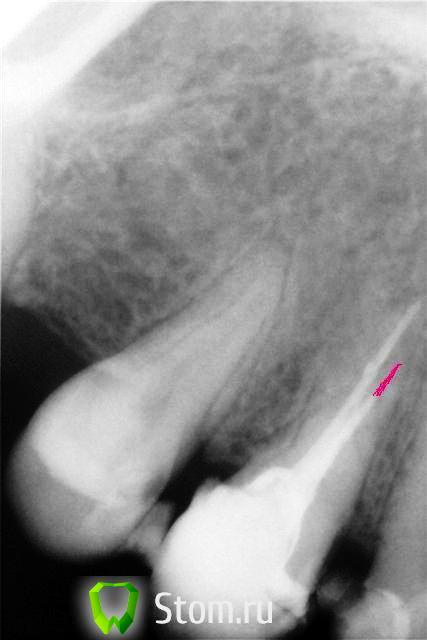

Scrabble Опубликовано 1 февраля, 2012 Поделиться Опубликовано 1 февраля, 2012 НСВ, верхушка срезана и проекция замысловатая. Это снимок до или после? Ссылка на комментарий

SanyaDok Опубликовано 3 февраля, 2012 Поделиться Опубликовано 3 февраля, 2012 Выведение гипохлорида за апекс серьезных осложнений вряд-ли вызовет,кроме боли при накусывании в ближайшее время.Может более интенсивной при близости гайморовой пазухи(ее слизистой),при расположении корня в ней или под ее слизистой.В вашем случае гайморова далеко и это-лимфаденит щечного узла,как реакция на раздражитель(имхо)-ничего страшного.И,как мне кажется есть недопломбировка одного из каналлов ,что тоже может давать боль и впоследствии периодонтит(судя по снимку). 2 Ссылка на комментарий